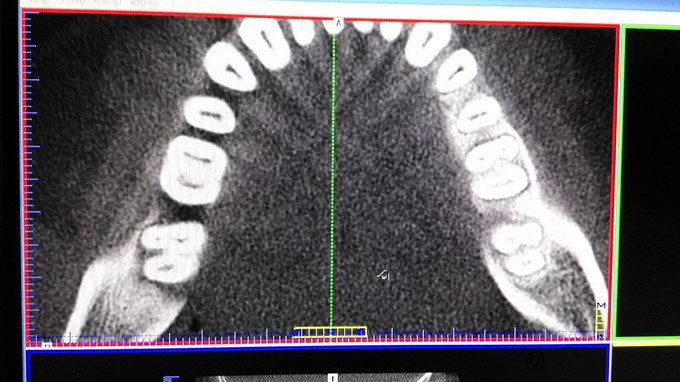

检查:右下7牙冠完整,近龈缘可见一突起脓包,少量脓血分泌物溢出,PD=10mm,余位点PD=3mm左右,叩痛(+),松动I度,电活力测试较正常牙迟钝。X线示:右下7牙槽骨水平吸收至根中,根分歧下低密度影像,远中根管增宽,可以根折。复拍CT:右下7根分歧下低密度影像,未达根尖,两根在舌侧融合,唇侧分开,唇侧无根柱,未见根折。